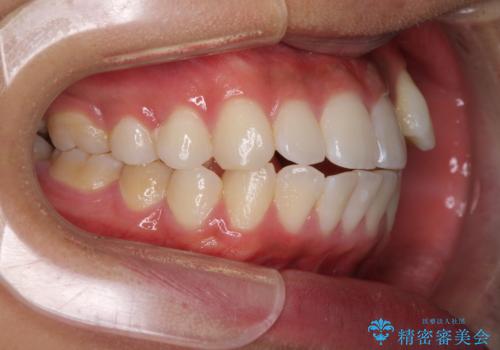

八重歯と奥歯のクロスバイト 上顎骨を拡大してインビザラインで矯正

- 八重歯を気にして来院された患者様です。

八重歯が著しいため、抜歯矯正も視野に入れて検討しましたが、臼歯の咬合関係は正常に近かったので、非抜歯矯正で進める方針としました。

上顎骨の幅が狭く、奥歯がクロスバイトとなっていたため、急速拡大装置を用いて上顎骨を側方拡大し、八重歯を収めるスペースを獲得しつつクロスバイトを改善することとしました。

上顎骨を思い通りに拡大できたため、当初の計画通りに非抜歯矯正で仕上げることができました。